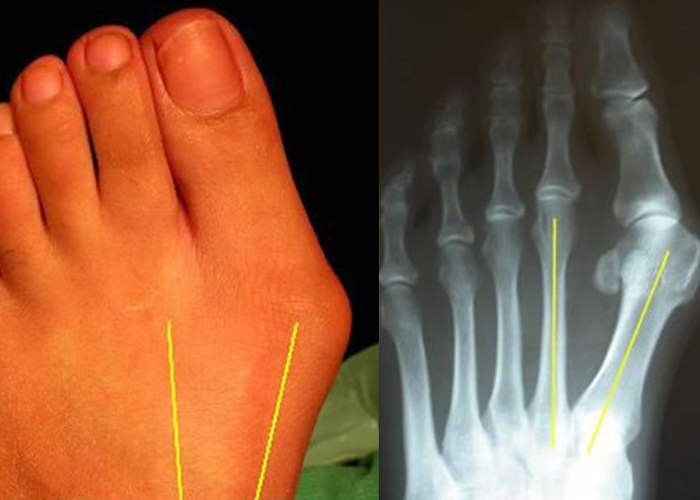

진단

발가락의 형태적인 변형만으로 진단가능하나, 정확한 진단을 위해 방사선 촬영으로 관절 구조와 뼈의 상태를 확인후 정량화 하여 평가합니다.